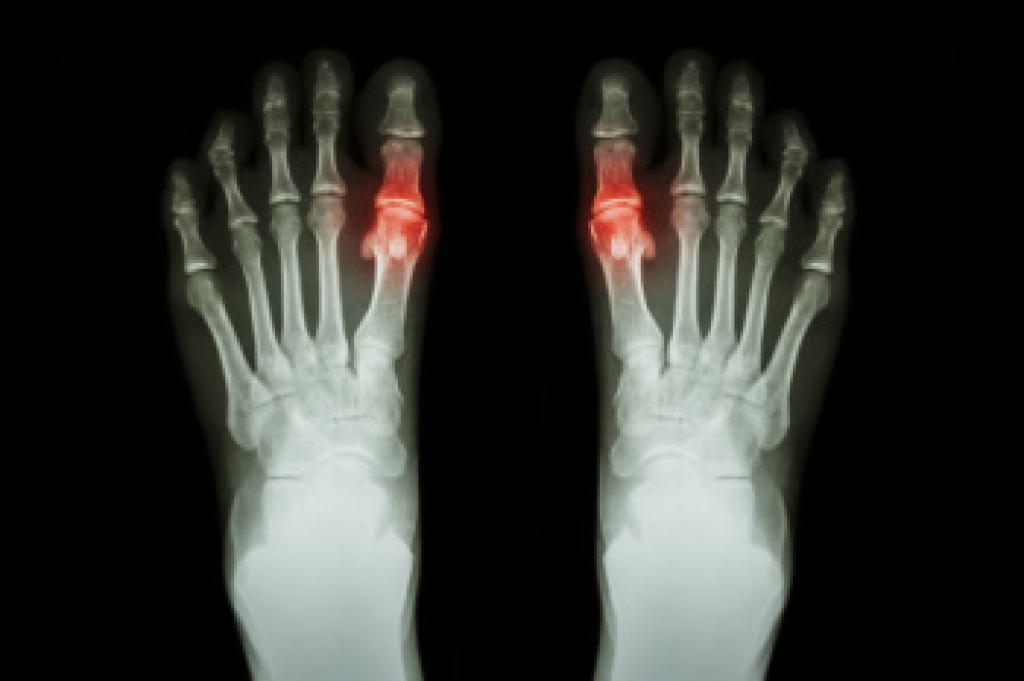

Arthritis, particularly osteoarthritis, is a common cause of foot pain and discomfort. Osteoarthritis is a degenerative joint disease that causes the cartilage in the joints to break down, leading to pain, stiffness, and swelling. In the feet, it can affect areas like the toes, ankles, and the arch. Common symptoms include joint tenderness, limited movement, swelling, and difficulty walking. The causes of osteoarthritis in the foot can range from age and genetics to previous injuries or repetitive stress. Over time, the wear and tear on the cartilage causes painful friction between bones. If you are experiencing foot pain or stiffness, a podiatrist can offer effective treatments. This type of doctor can recommend custom orthotics, pain management options, targeted exercises, or surgical procedures if needed. Seeking expert care early can help manage symptoms and improve mobility. If you are suffering from painful arthritis, it is suggested that you schedule an appointment with a podiatrist to get the relief you need.

Arthritis is a term that is commonly used to describe joint pain.  The condition itself can occur to anyone of any age, race, or gender, and there are over 100 types of it.  Nevertheless, arthritis is more commonly found in women compared to men, and it is also more prevalent in those who are overweight. The causes of arthritis vary depending on which type of arthritis you have. Osteoarthritis for example, is often caused by injury, while rheumatoid arthritis is caused by a misdirected immune system.

Understanding Gout and How Podiatrists Treat It

Gout is a type of arthritis caused by the buildup of uric acid crystals in the joints, leading to intense pain and inflammation. This condition typically affects the big toe but can involve other joints as well. Uric acid is a waste product that the body normally eliminates, but when it accumulates in excessive amounts, it can form sharp crystals that irritate the surrounding tissues. Podiatrists treat gout by first diagnosing the condition through physical exams and sometimes tests to measure uric acid levels. Treatment often involves medications to reduce uric acid levels, manage pain, and decrease inflammation. Podiatrists may also recommend lifestyle changes, such as dietary adjustments and weight management, to help prevent future flare-ups. Wearing supportive footwear and custom orthotics can also assist in alleviating pressure on the affected joints, promoting healing and comfort. If you have had one or more bouts of gout, it is strongly suggested that you are under the care of a podiatrist who can effectively treat and manage this condition.

What Is Gout?

Gout is a form of arthritis that is characterized by sudden, severe attacks of pain, redness, and tenderness in the joints. The condition usually affects the joint at the base of the big toe. A gout attack can occur at any random time, such as the middle of the night while you are asleep.